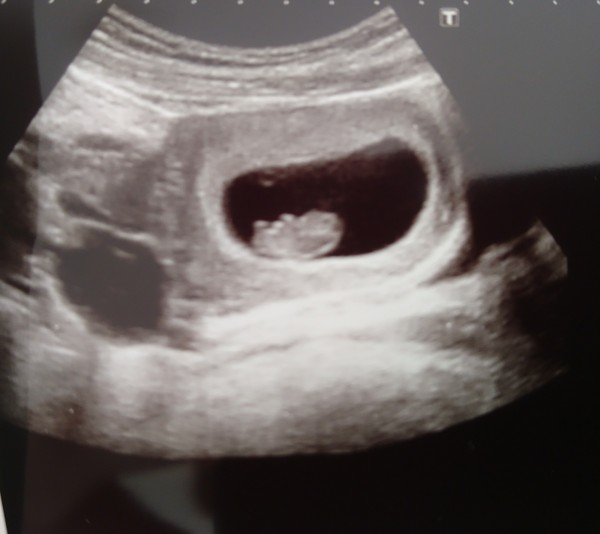

My little bean is okay and looking loads bigger compared to last week. Can't find any cause for bleeding so thinking it may just be old stuff clearing out.